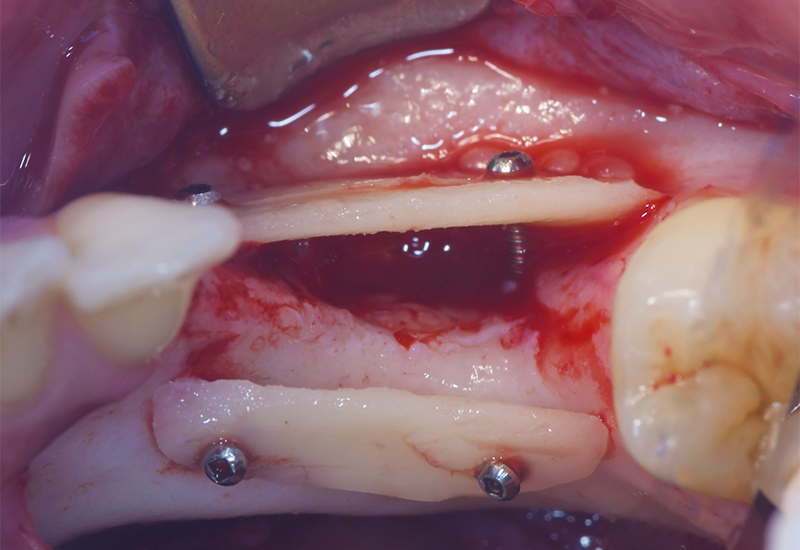

Fig. 06 : comblement du gap entre les lames osseuses autogènes à l’aide d’os particulaire autogène récupéré à l’aide d’un collecteur d’os..

Fig. 07 : ostéosynthèse des lames osseuses à l’aide de microvis Stoma®.

À 4 mois, on peut valider la bonne régénération osseuse au niveau du Cone Beam, lors de la planification implantaire et lors du temps opératoire de la pose des implants.

Fig. 09 : réouverture du site greffé 4 mois après la réalisation de la greffe osseuse et dépose des micro-vis d’ostéosynthèse.